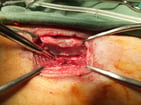

【下顎部扁平上皮癌】

下顎部にできた扁平上皮癌を切除しているところ。扁平上皮癌は浸潤性が強いため、骨にまで浸潤しているケースがある。そのため、あごの部位に限局していれば、あごの骨ごと切除する。